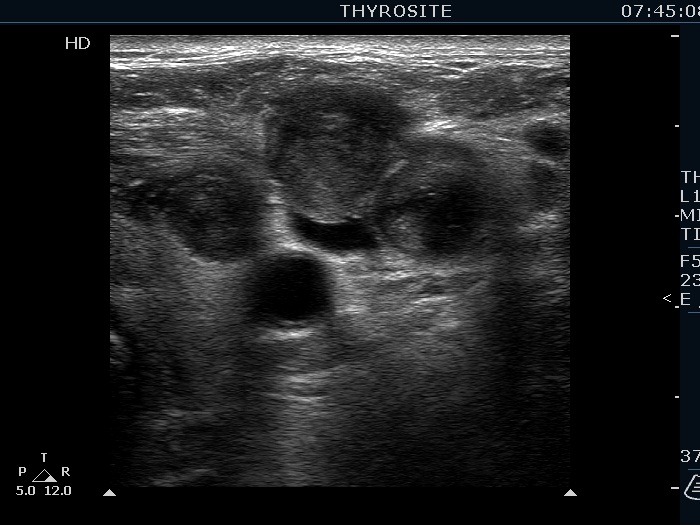

Ultrasonography. The right lobe was echonormal and presented several hypoechoic nodules. A large, inhomogeneous, partly deeply hypoechoic, partly minimally hypoechoic or echonormal mass occupied the left lobe. The borders of the tumor were irregular. There were multiple lymph nodules upper and lateral to the left thyroid lobe. The nodes had a heterogeneous pattern and lacked hilum. The vascularity was scanty both in the thyroid nodules and the lymph nodes.